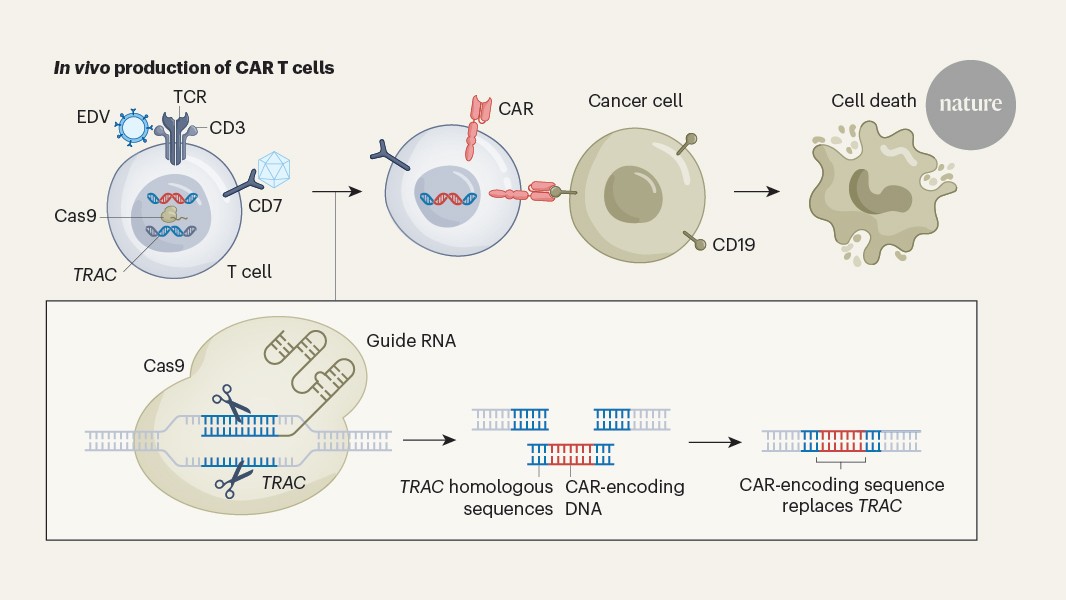

CRISPR makes enhanced cancer-fighting immune cells inside mice

Nature, Published online: 18 March 2026; doi:10.1038/d41586-026-00857-6Gene-editing technique promises a potentially safer way to create CAR T cells with a s...

A gene-editing method generates immunotherapeutic CAR T cells in the body

Nature, Published online: 18 March 2026; doi:10.1038/d41586-026-00634-5Laboratory-engineered immune cells called CAR T cells provide effective treatment for ...

In vivo site-specific engineering to reprogram T cells - Nature

Nature, Published online: 18 March 2026; doi:10.1038/s41586-026-10235-xStable and cell-specific transgene expression can be achieved through in vivo site-spe...